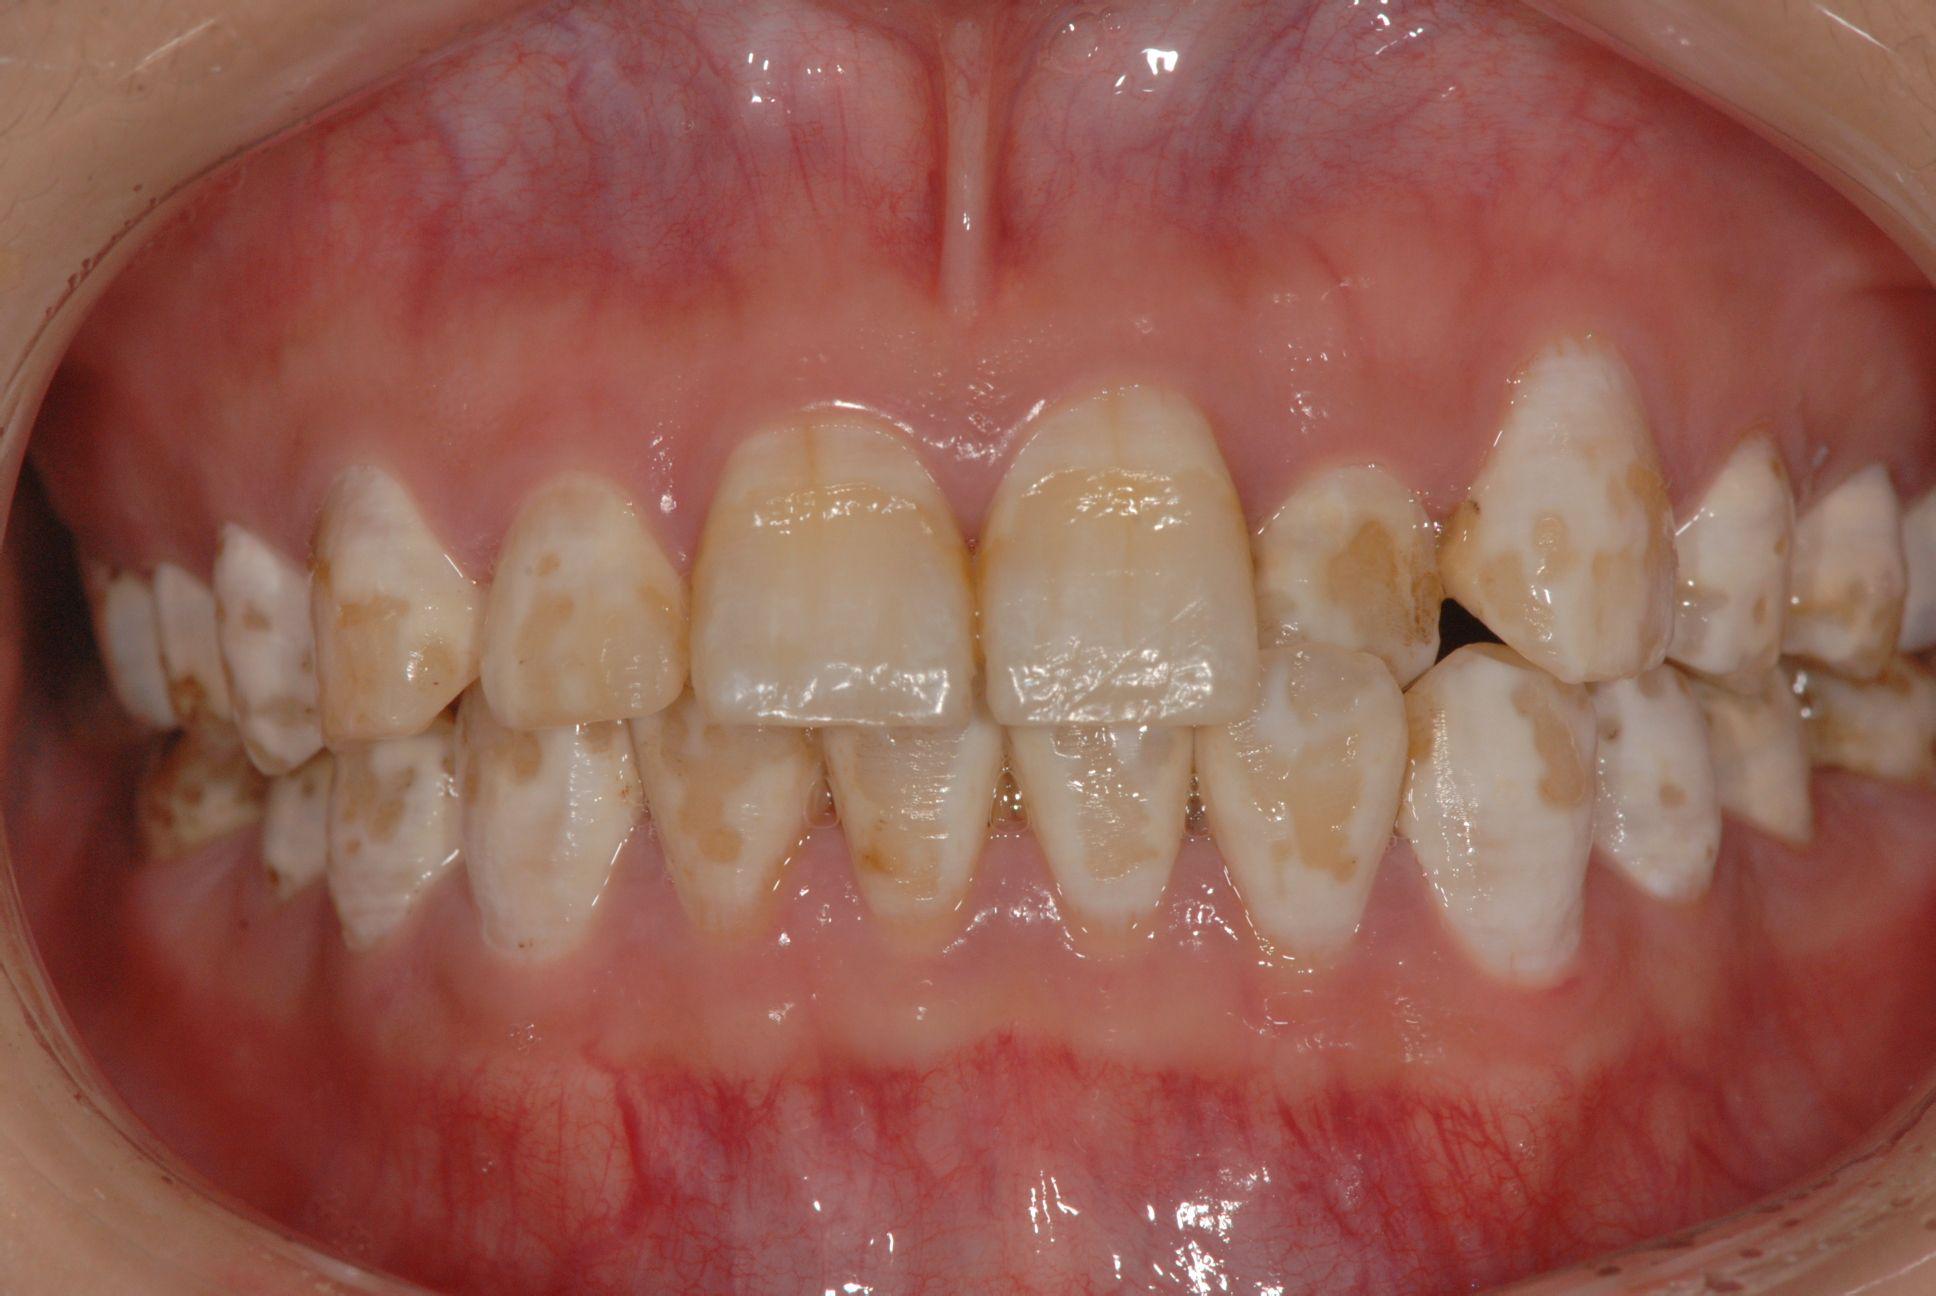

★轻度:轻度的氟斑牙牙齿整体颜色还可以,就是有些黄斑,白斑的面积不大,往往在门牙上,影响美观。

★中度:中度的氟斑牙,牙齿有轻度或者缺损很少,就是有大面积的牙齿颜色发黄,黄斑。氟斑牙不治有什么危害?

★重度:重度氟斑牙,牙齿有缺损,有些甚至磨损的比较严重了。颜色也黄的很厉害,甚至有部分已经发暗发黑。